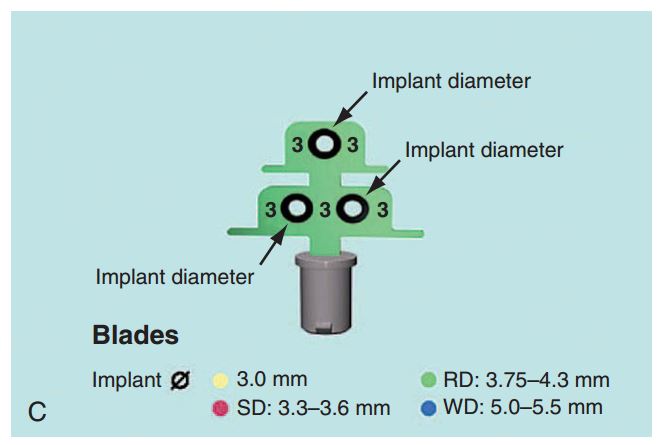

Dụng cụ hướng dẫn định vị Implant

Giúp xác định đúng vị trí đặt Implant và lựa chọn đường kính Implant tối ưu nhất (H2.18). Bộ hướng dẫn ITT gồm có:

– Tấm Titan, giúp hướng dẫn đường kính và vị trí của 1 – 2 Implant.

– Pin đo đạc có phần mở rộng, giúp hướng dẫn đường kính và vị trí Implant ở bệnh nhân không răng.

– Pin song song, để xác định độ song song của Implant.

– Cán của tấm Titan, giúp cầm nắm và đặt tấm Titan vào trong miệng 1 cách an toàn.